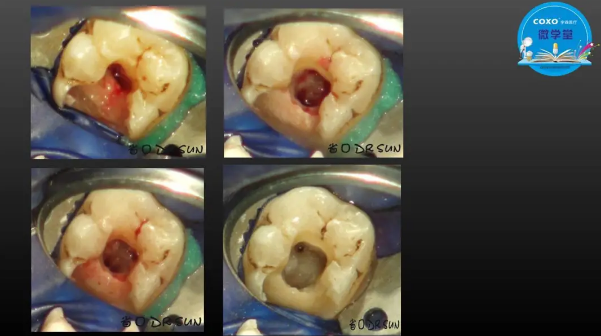

主任醫(yī)師,牙體牙髓副主任, 廣東省口腔醫(yī)院牙體牙髓科 主任醫(yī)師。2003年碩士研究生畢業(yè),研究方向為牙體牙髓病學,擅長于牙體牙髓病的診斷、齲齒、牙髓炎、根尖周病的治療以及前牙美容修復。